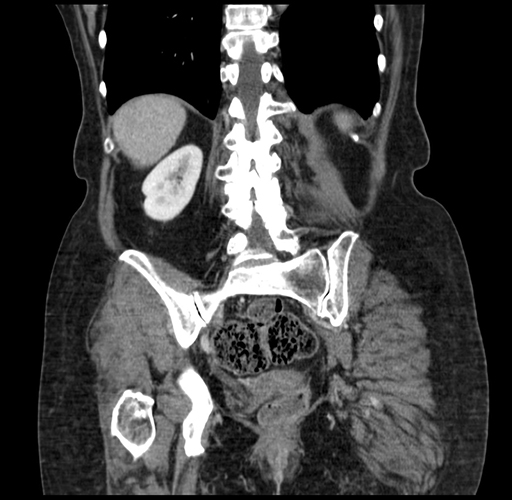

Coronal Venous